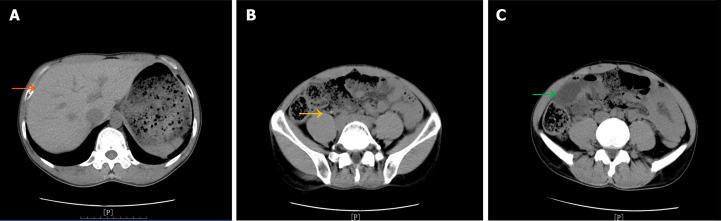

This report describes the case of a middle-aged man initially suspected of having acute appendicitis, which rapidly progressed to acute peritonitis with concomitant intestinal obstruction observed during preoperative assessment. Surgical exploration confirmed the diagnosis of Meckel's diverticulum-induced internal hernia, accompanied by intestinal obstruction and necrosis. In addition, the hernial ring base exhibited entrapment resembling a surgical knot.

本报告描述了一名中年男性的病例,该患者最初被怀疑患有急性阑尾炎,在术前评估中迅速发展为急性腹膜炎,并伴有肠梗阻。手术探查证实诊断为梅克尔憩室引起的内疝,伴有肠梗阻和坏死。此外,疝环底部出现类似手术结的卡压。